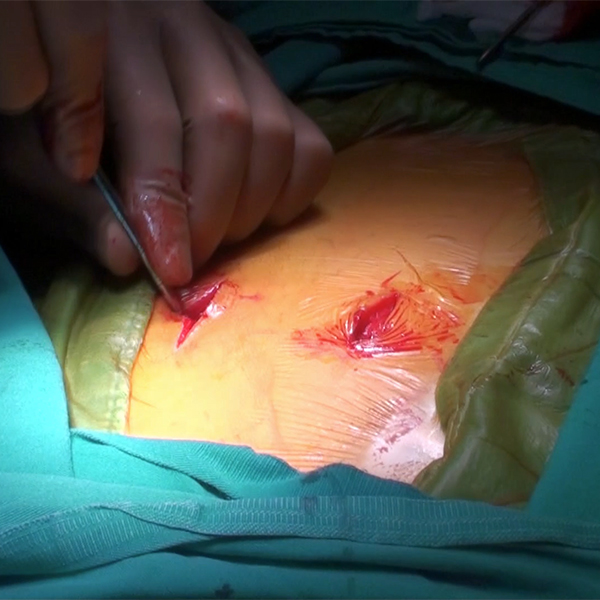

Artroplasti Kalça Protezi

Umut Ocak

Norm Akademi

- Kalça Anatomisi

- Kalça Kırıkları

- Osteosentez

- Protez Uygulamaları

- Kalça Protezi Tarihçesi

- Parsiyel Kalça Protezi

- Femoral Stem Çeşitleri

- Bipolar Kalça Protezi Uygulaması

- Total Kalça Artroplastisi

- Kalça Protezi Ameliyatları

- Uygulamalar

- Asetabular Kaplar

- Çimentolu ve Çimentosuz Femoral Stem

- Diz Protezleri

- Total Diz Protezi

- Unicondylar Protez